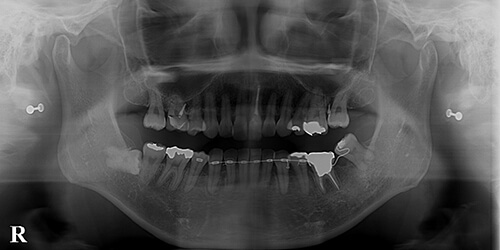

【治療中】

挺出とアップライト(後ろに起こすこと)を同時にもしくは交互に行っているところです。

噛み合わせの関係もあって挺出し過ぎているのもあり、同時に圧下もしなければいけなくなりました。

相当な力が必要なため、アンカーは反対側の4番(第1小臼歯)まで伸ばしてあります。

ワイヤーだけの圧下が困難と判断し、骨の内側と外側に一時的なミニインプラントを埋入し、このインプラントをアンカーに8(親知らず)の圧下と移動を試みているところです。